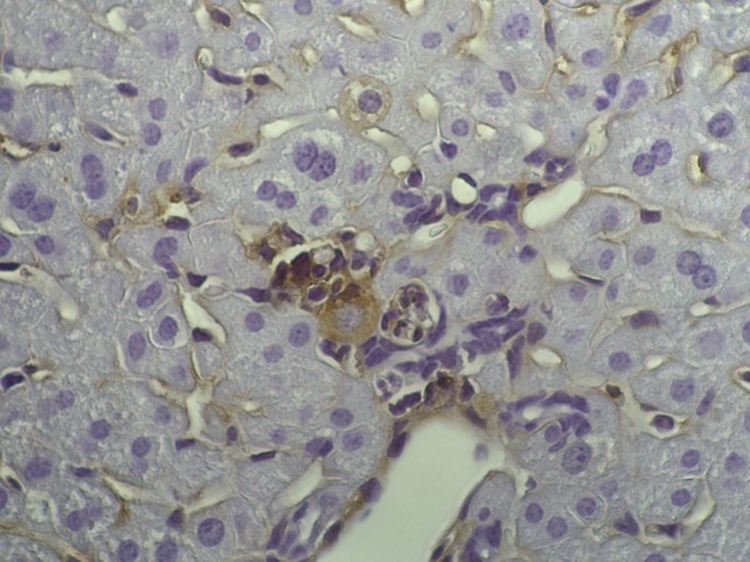

Immunzellen unter dem Mikroskop.

(Foto: picture alliance / dpa)